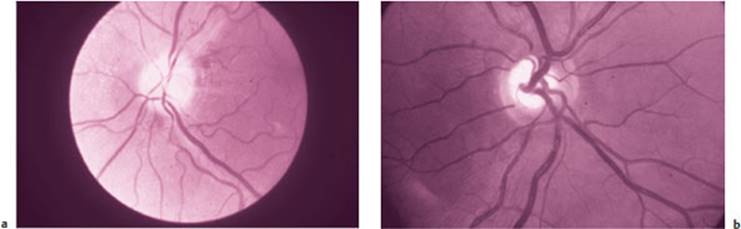

Ophthalmoscopy. Inspection of the optic nerve papillae (optic discs) with the ophthalmoscope is an important technique for assessment of the optic n. Abnormal pallor indicates an optic nerve lesion (Fig. 3.4). In addition, inspection of the eye grounds can provide evidence of elevated intracranial pressure: in papilledema, the papillae are raised and hyperemic, and their margins are blurred. Enlarged retinal veins indicate impaired venous drainage due to intracranial hypertension (cf. Fig. 11.2, p. 183). A raised papilla with blurred margins can also be a sign of an inflammatory process affecting the optic n. (p. 182).

Fig. 3.4 Optic disc (papilla) of the right eye. a Pale, atrophic disc, b Normal disc (images kindly provided by the Department of Ophthalmology, University of Berne.) (For the color version of this figure, cf. Plate 1)